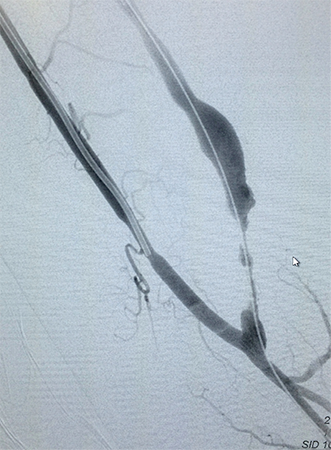

Tratamento de Aneurismas de Aorta, Periféricos ou Vicerais

É o tratamento de artérias dilatadas por métodos endovasculares pouco invasivos. O procedimento pode alterar de acordo com a região localizada, do tamanho e da condição do aneurisma. Atualmente a cirurgia vascular dispõe em seu arsenal para o tratamento de aneurismas, um método seguro e menos invasivo que a cirurgia convencional. O tratamento endovascular para aneurismas de aorta, viscerais e periféricos possibilita uma melhora na qualidade de vida dos pacientes de uma forma menos agressiva, objetivando evitar as principais complicações dessas doenças. São utilizados dispositivos de implante totalmente percutâneo e o procedimento é realizado em local específico para estes casos. Após detalhada análise de exames complementares: ultrassom, angiotomografia, angiorressonância, o cirurgião vascular opta pela melhor alternativa de tratamento baseado na anatomia da doença e no perfil de cada paciente.